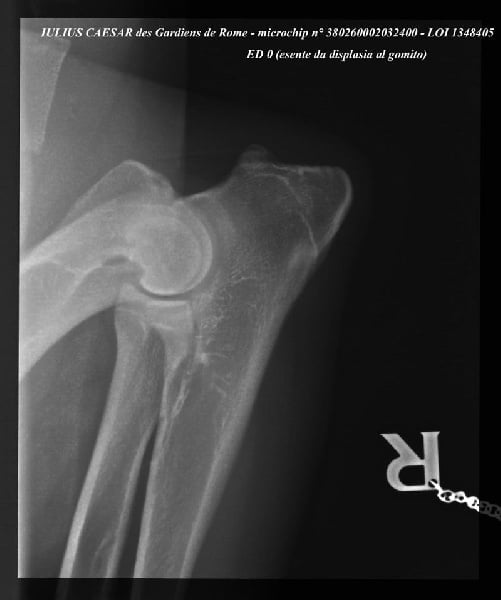

| Puce | 380260002032400 |

| N° origine | LOI 1348405 |